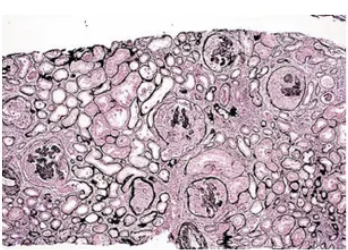

Microscopía óptica de la enfermedad de Berger

Glomérulos normales o con ensanchamiento mesangial

Presencia de leucocitos en capilares glomerulares

Lesiones visibles: la curación lleva a esclerosis focal y segmentaria, necrosis con formación de estructuras semilunares

En la inmunofluorescencia de la enfermedad de berger se pueden ver depósitos de ______, puede haber ___ y ____ y cantidades menores de IgG o IgM

IgA; C3; properdina